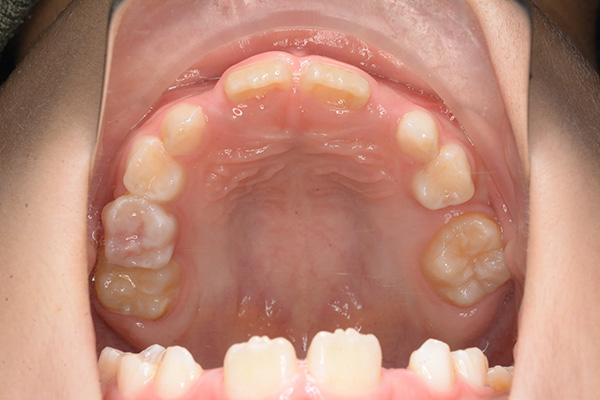

動的治療開始前(9歳7ヵ月)

動的治療開始前

(9歳7ヵ月)

IOP

口腔内所見 over jet -2.5mm、over bite 2.0mm、大臼歯関係はⅠ級 。Hellmanのdental ageはⅡCであり前歯部は反対咬合を呈していた。

パノラマ所見 上顎アーチレングスディスクレパンシー(-)であるが、その他の異常所見は認められなかった。